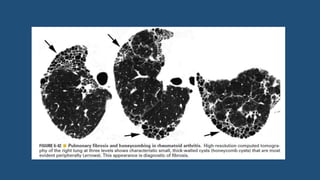

Honeycombing

• Presence of small cystic spaces with irregularly thickened walls

composed of fibrous tissue.

• Honeycomb cysts often predominate in the peripheral and sub-

pleural lung regions regardless of their cause.

• Irreversible – no t/t required